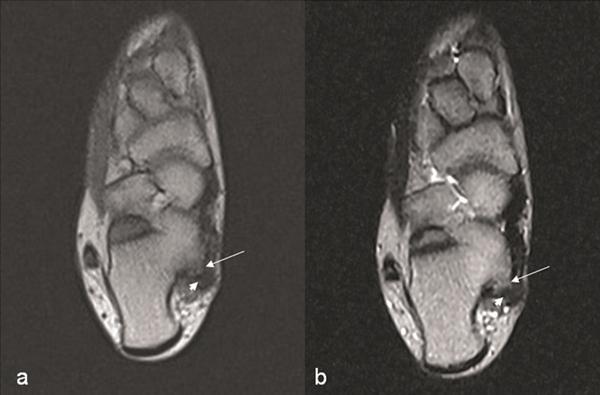

We report the clinical and radiologic findings of a calcaneal osteochondroma with an extremely rare placement and painfull, rapid reccurence following surgical excision in a skeletally mature female. The lesion showed growth the first-operation later and was re-operated. Histopathological examination did not show malignancy.

我们报告了一名骨骼成熟女性跟骨骨软骨瘤的临床和影像学表现,该肿瘤位置极其罕见,手术切除后疼痛且迅速复发。病变在首次手术后出现生长并再次接受手术。组织病理学检查未显示恶性。